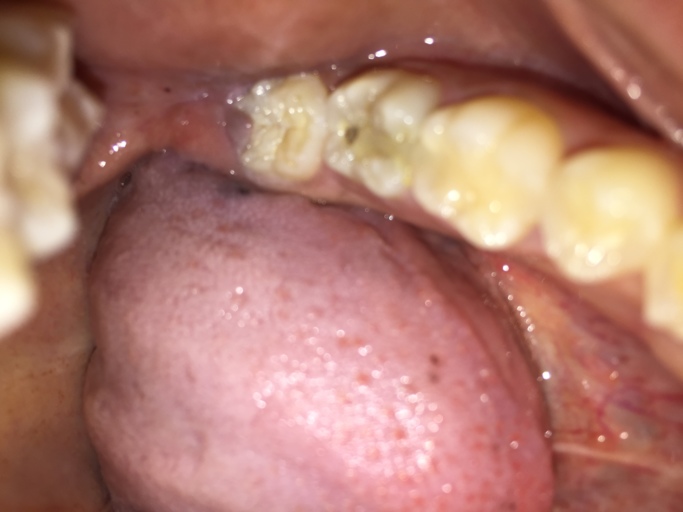

I believe you submitted your question twice, once without a picture. Looking at the picture, it appears as though there is recurrent decay around the restoration.  More than likely the restoration broke when the tooth structure underneath it became weak.  Schedule an appointment with your dentist to have the tooth evaluated.  If there is in fact decay under the restoration, you want to have it removed and the restoration replaced as soon as possible.  This will reduce the chances of a more extensive restoration as well as the decays proximity to the nerve of the tooth.